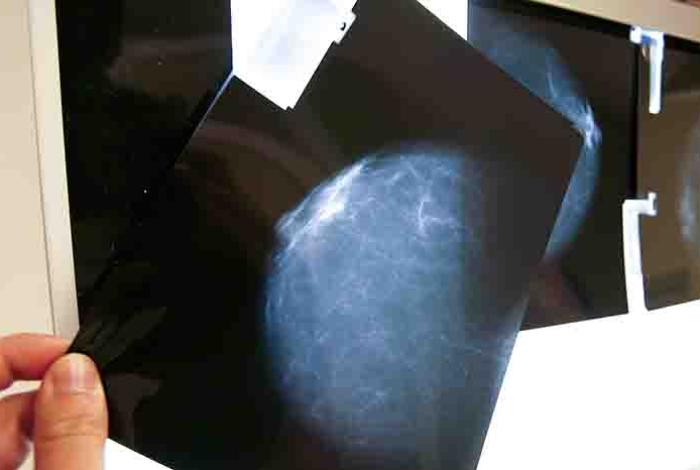

Relacionan la alta densidad mamaria con los tumores más agresivos y de peor pronóstico

El estudio ha analizado la relación entre densidad mamográfica y los subtipos de cáncer de mama y también la posible influencia del índice de masa corporal y el estado menopáusico La entrada Relacionan la alta densidad mamaria con los tumores más agresivos y de peor pronóstico se publicó primero en La Voz de Michoacán.